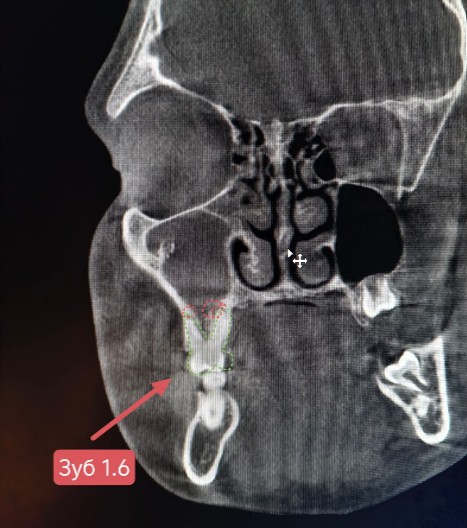

Фарингоскопия: слизистая глотки розовая, влажная. Миндалины не увеличены, без патологического содержимого. В области десны зуба 1.6 отмечается незначительная отечность, гиперемия слизистой оболочки, при пальпации слабая болезненность.

Проведена компьютерная томография околоносовых пазух, которая подтвердила наличие правостороннего гемисинусита (воспаление нескольких пазух с одной стороны), как следствие периодонтита зуба 1.6.

На снимке детально представлена область пораженного зуба 1.6.

- Пациенту рекомендована консультация стоматолога с целью санации очага инфекции со стороны полости рта (лечение периодонтита зуба 1.6).